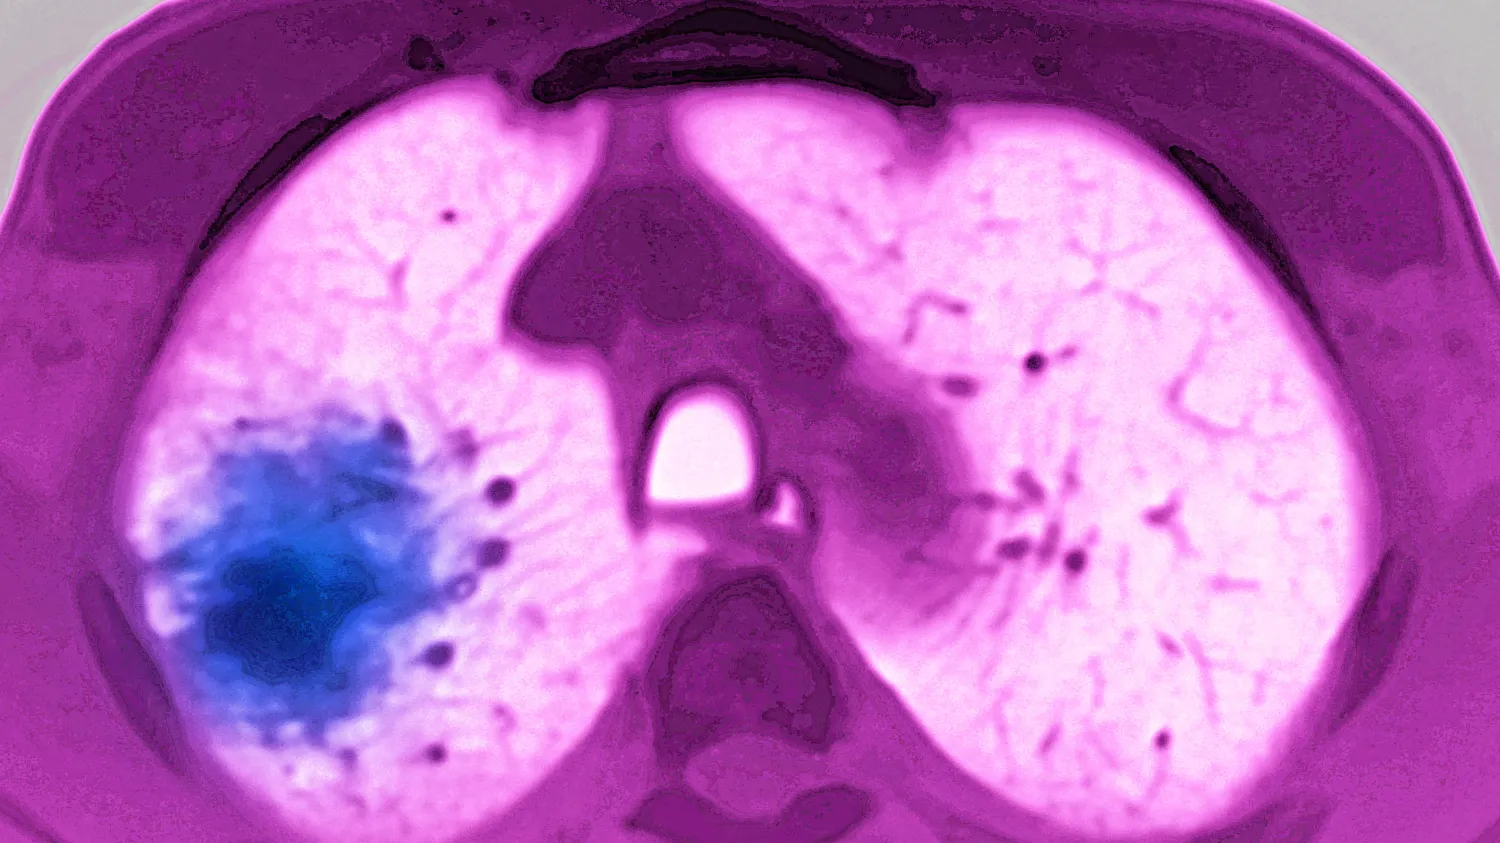

My doctoral and postdoctoral research centered on refining molecular portraits of cancer in the light of their evolutionary and ecological features, with the goal of advancing genomic diagnostics. In research faculty and industry leadership roles, my interest has broadened to developing digital biomarkers that identify high-risk patients who are currently overlooked, improving algorithm performance in diverse clinical settings, and exploring the underlying pathophysiological mechanisms.

- Biswas et al. Nature Medicine (2019). A Clonal Expression Biomarker Associates with Lung Cancer Mortality.

- Biswas et al. Nature Cancer (2025). Prospective Validation of ORACLE, a Clonal Expression Biomarker Associated with Survival of Patients with Lung Adenocarcinoma.